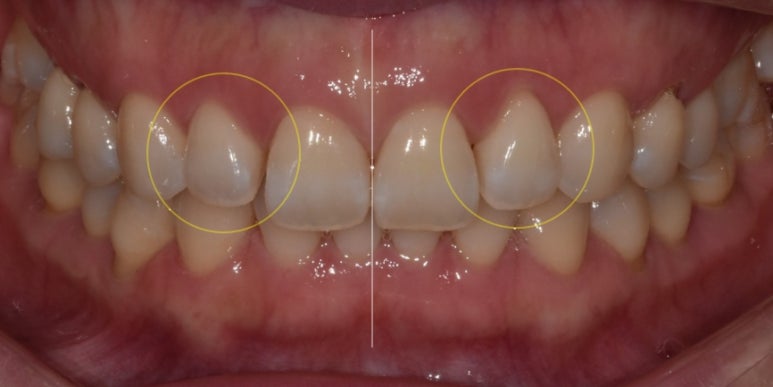

환자분은 교정을 진행하시어 치아 배열은 고르신 편이었지만, 대문니 양옆 치아(상악 측절치)가 벌어져 있어서 개선을 위해 내원해 주셨습니다.

그리고 (전) 사진을 보면 윗니 정중앙 라인이 아랫니 중앙 라인과 맞지 않는 것을 확인할 수 있는데요.

(전) 2022-07-13, (후) 2022-07-19

라미네이트를 통해 치아가 맞물렸을 때 정중선을 맞추어 치아가 더 고르게 보일 수 있도록 진행하였습니다.

또한 최초 고민이셨던 상악 측절치 사이 틈새도 보철물을 통해 공간을 채워드렸고요.

라미네이트는 최소삭제로 진행되었으며, 전체적인 치아 형태와 색상이 이전보다 개선된 것을 확인하실 수 있습니다. ^^